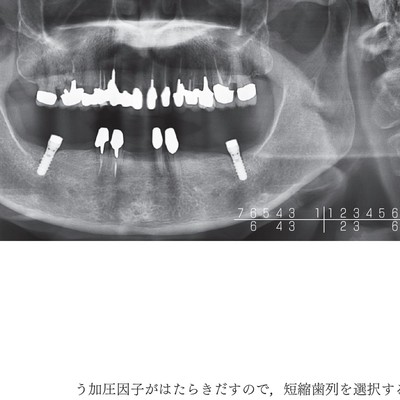

見る目が変わる! 「欠損歯列」の読み方,「欠損補綴」の設計 | 本多。欠損歯列」の読み方,「欠損補綴」の設計。欠損歯列における犬歯の重要性│設楽 幸治先生 | Doctorbook academy。見る目が変わる! 「欠損歯列」の読み方,「欠損補綴」の設計本多正明・宮地建夫・伊藤雄策・武田孝之【編著】2013年01月10日 A4変型判 272頁17,600円(税込)クインテッセンス出版裁断済みです。。日本の医療現場にとって、最も大切な要素の1つ、欠損歯列の拡大予測

• 日本の医療現場にとって、最も大切な要素の1つ、欠損歯列の拡大予測